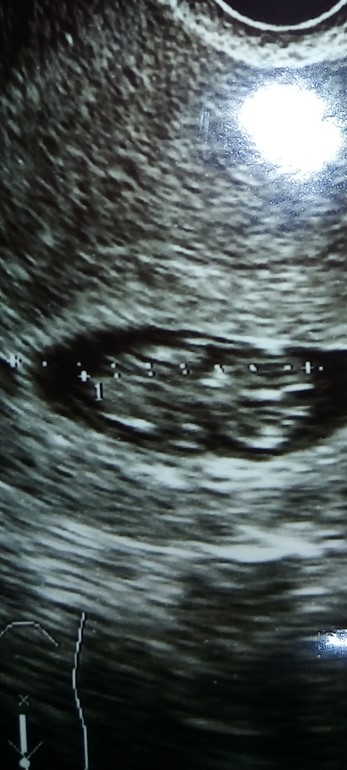

УЗИ, КТГ, доплер20 сентября была на узи, ктр 27 мм, а сегодня 26 сентября узи в другом месте 29.7 мм. Спрашиваю с тем, что правильно ли намерила узистка сегодня ктр, т.к. по фото видно, что стрелочка не на самом краешке головки. Или мне стоит бить тревогу? Чсс было 166, а сегодня даже не измерили, сказала только, что очень активный эмбриончик, сердечко видно как бьется.

1 фото сделано 20 сентября, видно вроде по стрелочкам как измерен.